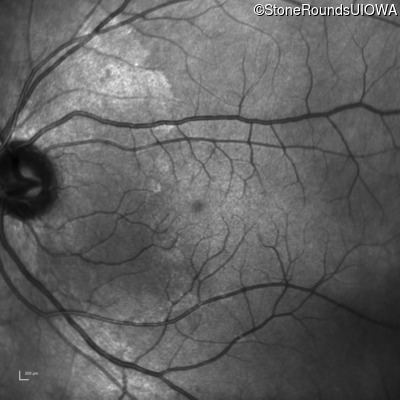

Infrared Fundus Photograph - Right - 20/20

Exemplar

Infrared Fundus Photograph - Left - 20/20 -2